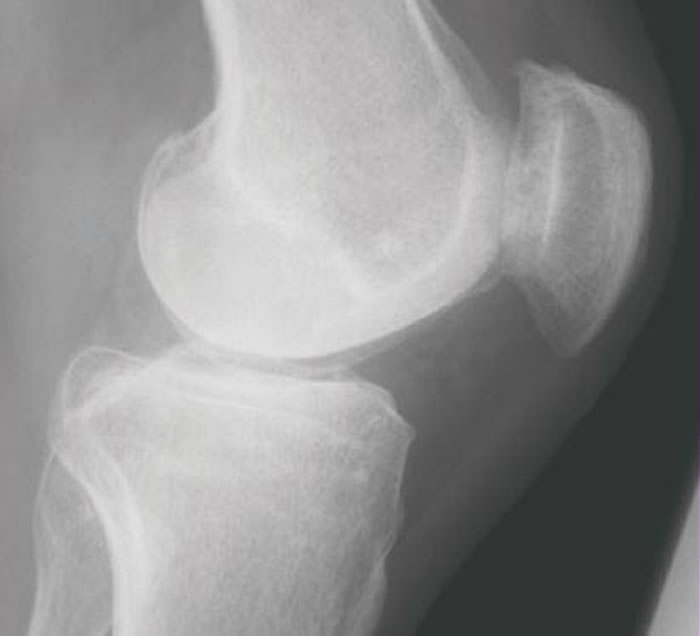

骨关节炎是最常见的炎症之一。然而,目前可以改善生活质量的最有效治疗手段是替换关节。